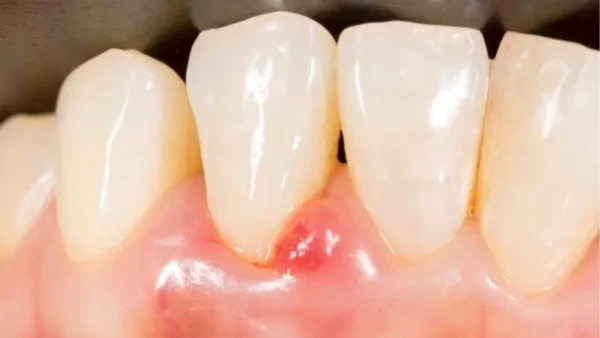

Có mủ hoặc tụt lợi quanh răng sứ

Khi bệnh tiến triển nặng, vùng lợi quanh răng sứ có thể xuất hiện mủ, kèm theo tình trạng tụt lợi, lộ chân răng. Nếu không điều trị sớm, viêm lợi có thể dẫn đến viêm nha chu, ảnh hưởng đến tuổi thọ của răng sứ và răng thật bên dưới.